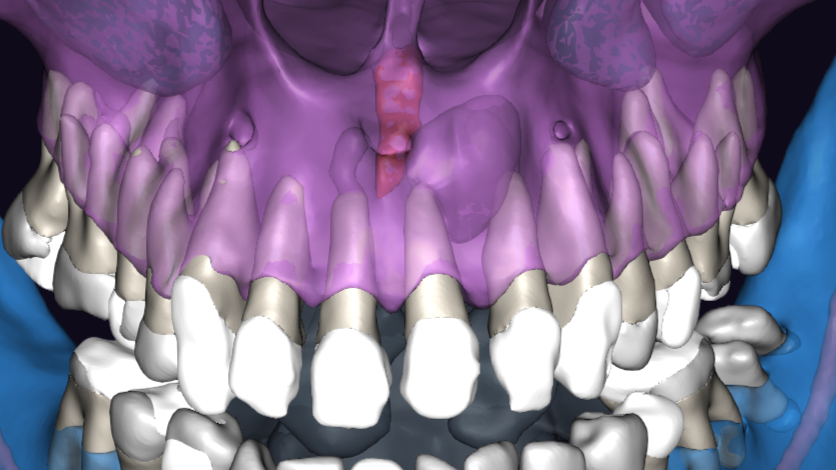

ЗД исследование перед операцией. Виден обьемный дефект в области зубов 21, 22 с вовлечением резцового канала. Размеры

Киста в области зуба 2.1

Киста в области зуба 2.2